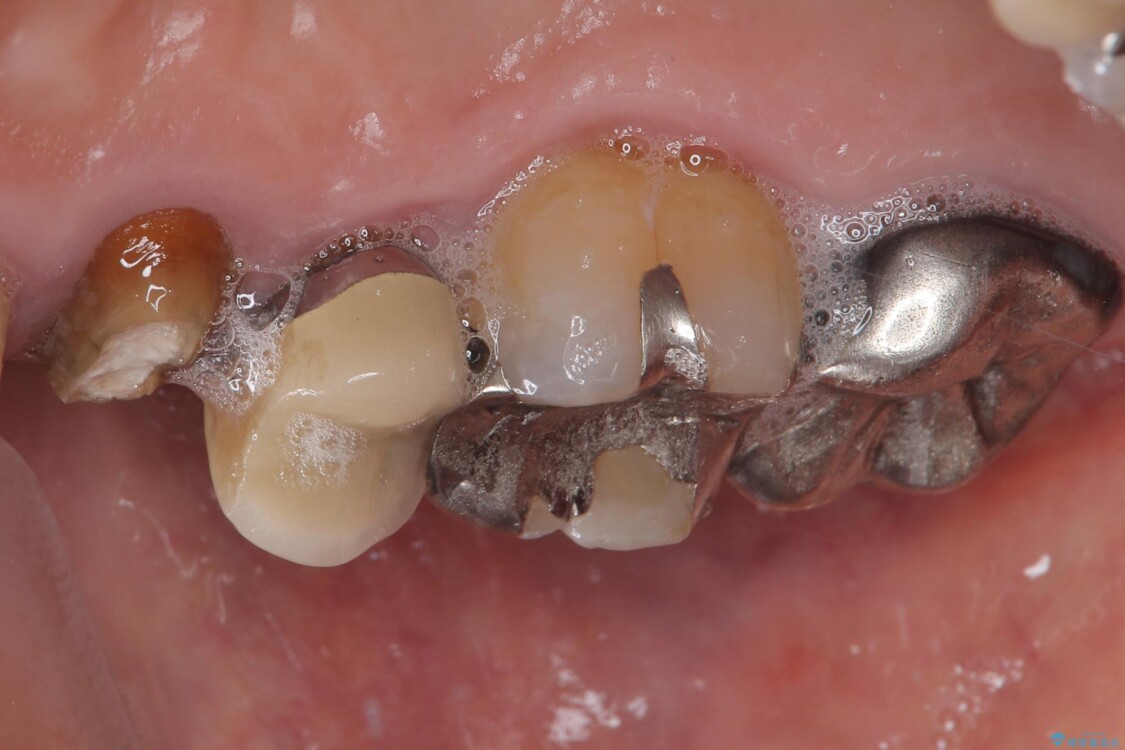

「以前治療した歯の被せものが外れてしまった」とのことで、右上の小臼歯の被せもの脱離を主訴に来院されました。

診察の結果、被せもの(クラウン)だけでなく、土台(コア)ごと外れてしまっている状態でした。根管治療済みの歯ではありますが、今回患者様のご希望により、根管治療の再治療は行わず、補綴処置のみを行う方針となりました。

• 自然な美しさと強度を両立!右上小臼歯の被せもの脱離に対する審美補綴治療 治療前画像